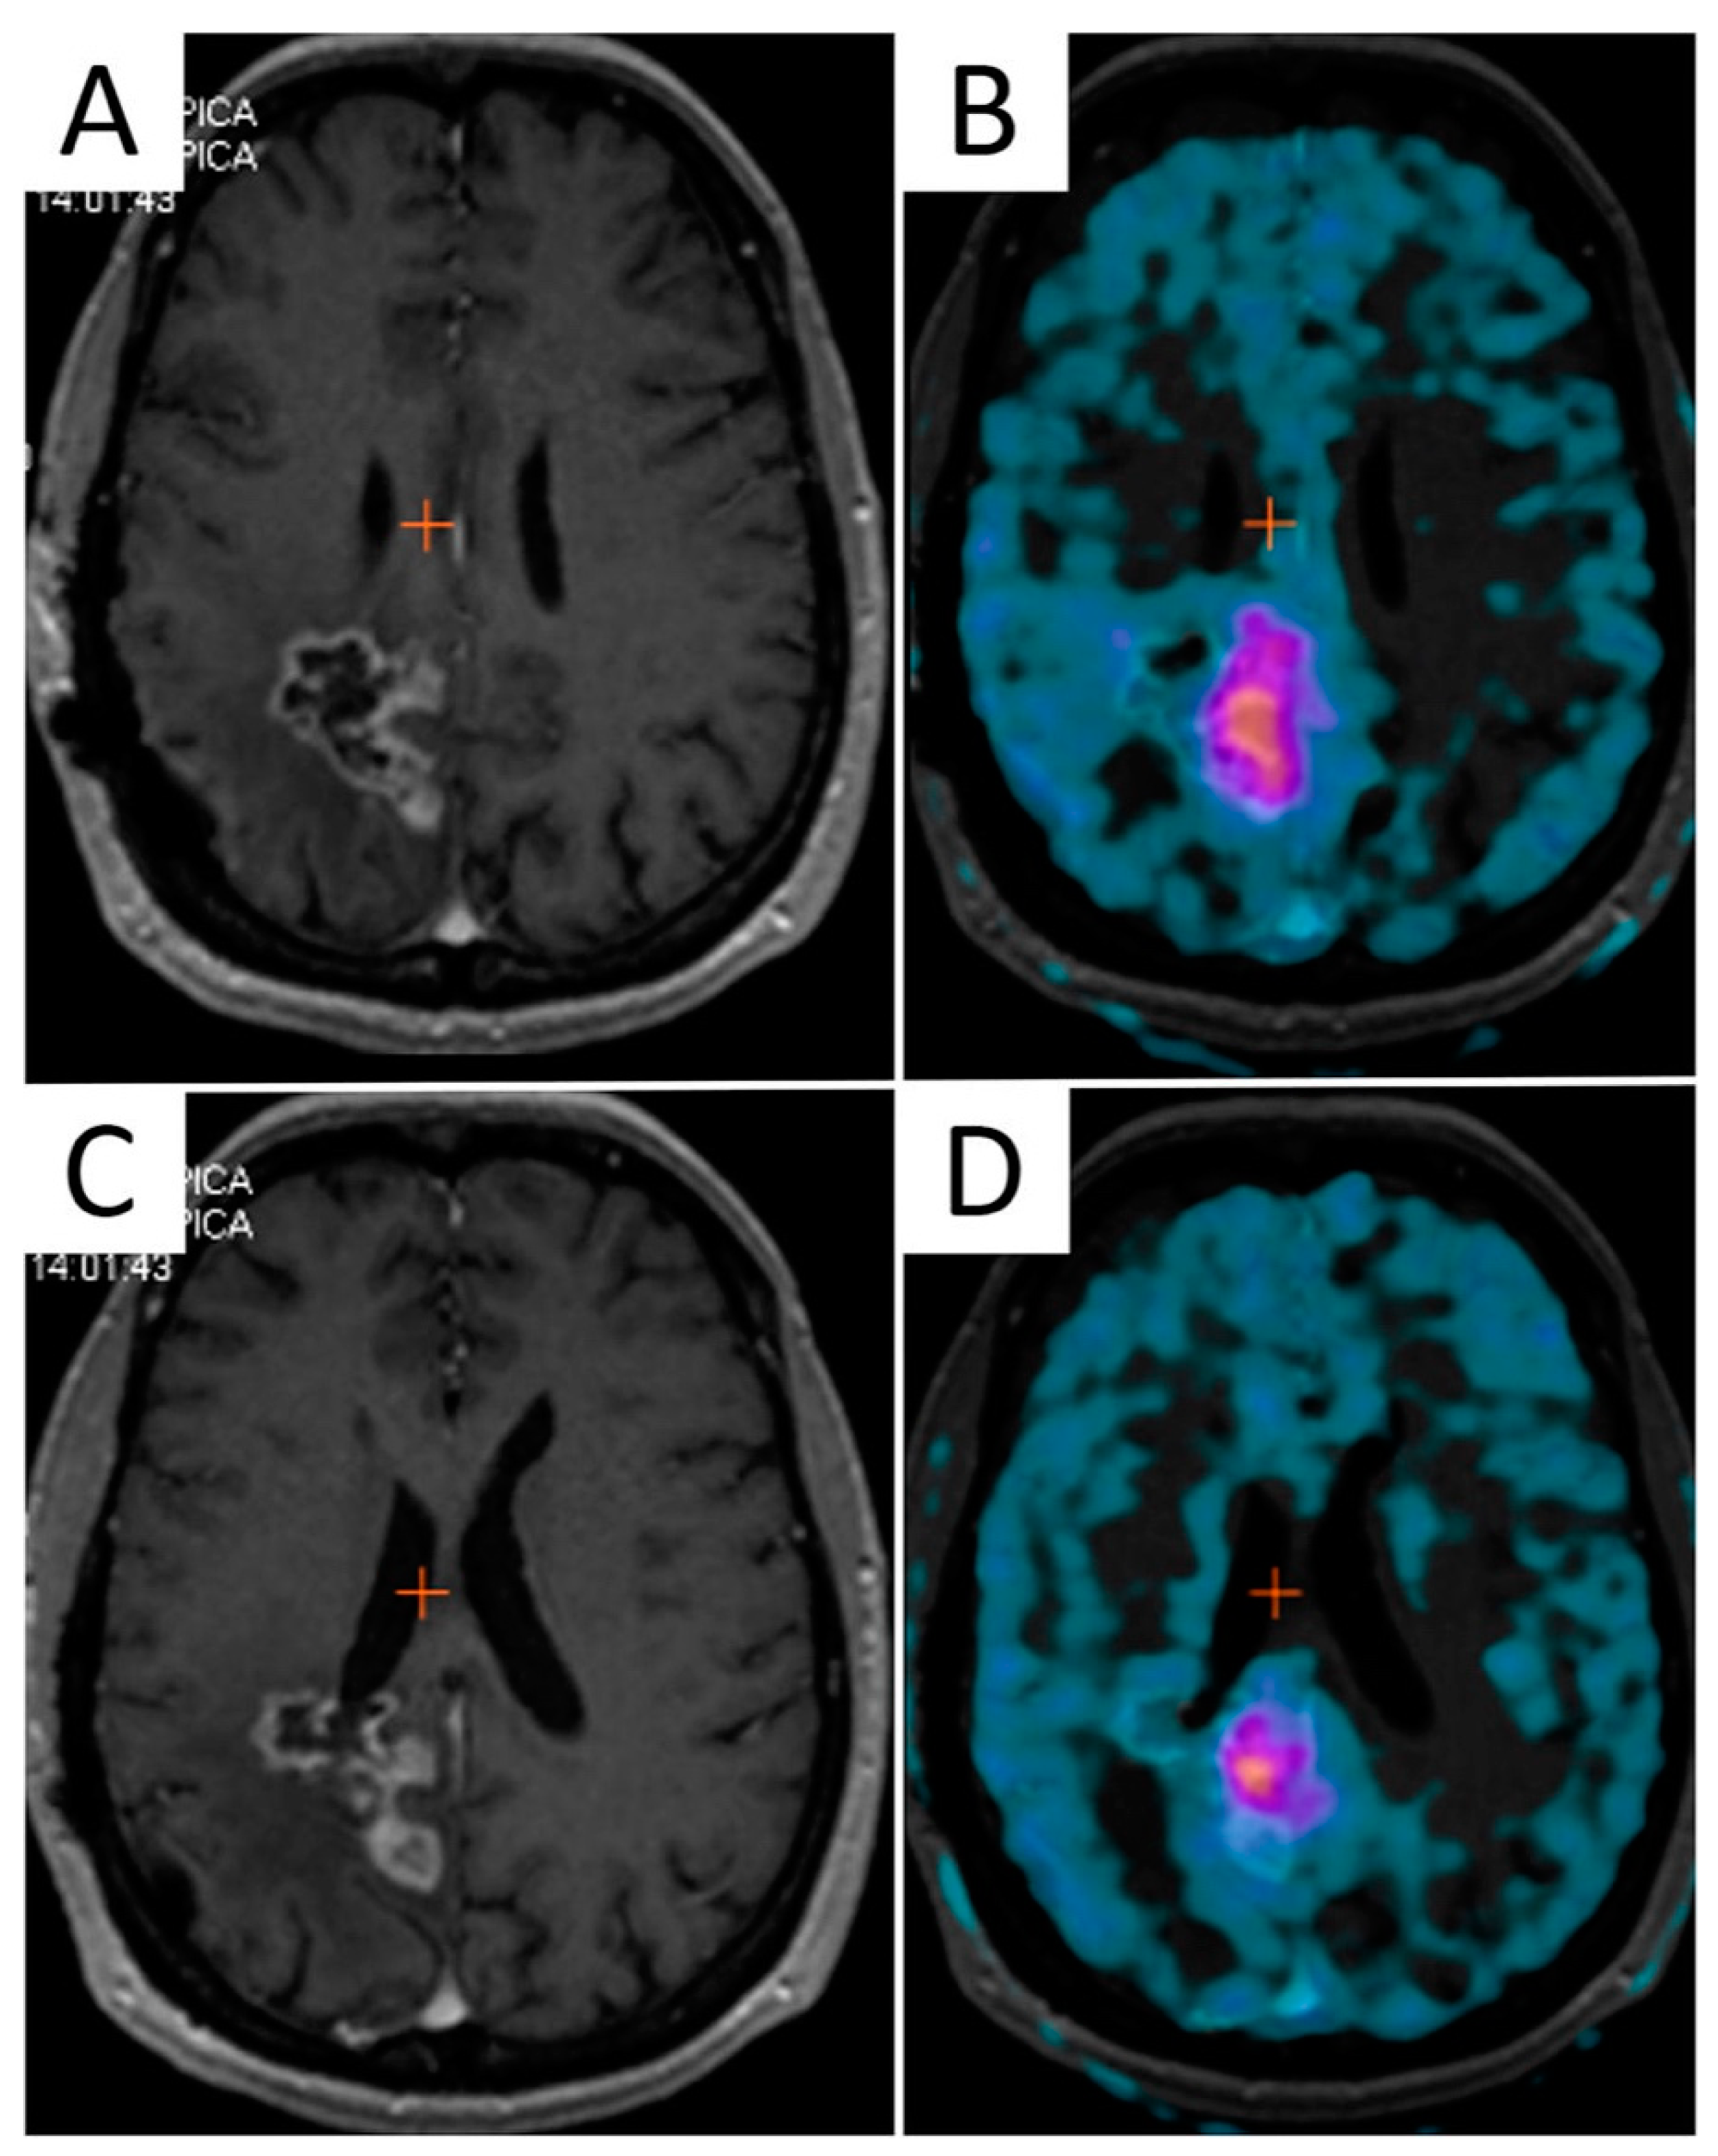

In recurrent gliomas, standard procedures have not yet been established. However, the aim is to limit the re-irradiated volume to the absolutely necessary, i.e., to the active tumor region, to enhance efficacy and decrease possible neurotoxicity. The delineation of tumor volume should, therefore, be restricted to the contrast-enhancing T1 abnormality. Unfortunately, anatomical contrast-enhanced T1-weighted MRI is not suited for differentiating tumor progression from radiation necrosis and therapy-related changes [95,171,172]. For these reasons, imaging techniques capable of better detailing the entire extent of tumor recurrence and patterns of infiltration are needed to optimize radiation treatment volumes [51] (Figure 5).

Figure 5.

Integration of F-DOPA PET/CT in a LINAC-based radiosurgical planning of a 55-year-old female patient with recurrent GBM. (A) shows GTV based on contrast-enhanced T1-weighted MRI images; (B) shows remarkable F-DOPA uptake extending beyond contrast-enhancement. The final target volume was delineated by taking into account the F-DOPA-positive signal (C). Three-month follow-up (D) shows tumor progression at the site of pre-RT increased F-DOPA uptake, despite salvage irradiation.